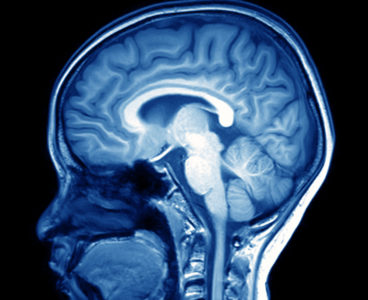

Neurons Reliably Respond to Straight Lines

Single neurons in the brain’s primary visual cortex can reliably detect straight lines, even though the cellular makeup of the neurons is constantly changing, according to a new study by Carnegie Mellon University neuroscientists, led by Associate Professor of Biological Sciences Sandra Kuhlman. The study’s findings, published in Scientific Reports on Oct. 16, lay the…